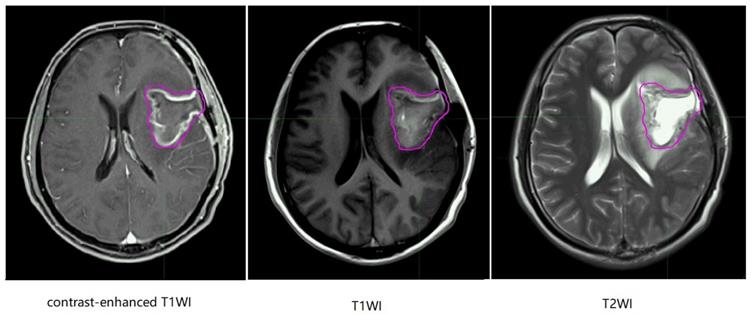

In the MR images of glioma patients, we delineated the gross tumor volume and recurrence tumor volume according to the regular MR images. As showed in Figure 8 and Figure 9, we tried to find the radiomics signature of tumor region without the peritumoral edema region.

Figure 9

Representative recurrence patient's regular brain MRI images, the purple line and the blue line represent gross tumor volume of primary tumor and gross tumor volume of recurrent tumor. T1WI, T1 weighted image; T2WI, T2 weighted image.

J Cancer Image